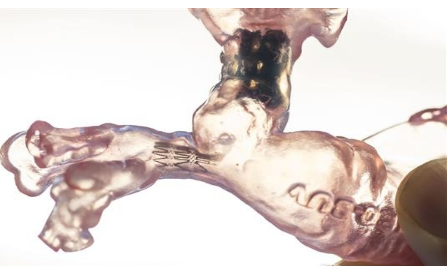

使用Nate的心髒CT掃描數據,醫院團隊能夠創建阻塞區域的3D打印模型。Ing博士可以製作一個特殊的小型支架,以適應從狹窄動脈的3D模型。結果是成功的:Nate的氧水平隔夜得到了改善。

到2017年1月,Nate終於準備好了下一個心髒手術。1月19日,Ing博士插入了第二個甚至更小的支架,他塑造了Nate右肺動脈的3D打印模型。開放心髒手術在洛杉磯兒童醫院導尿實驗室進行,大量的國際心髒病學家通過實況視頻觀看。Ing博士和他的團隊成功地開放了Nate的右肺動脈。嬰兒的氧氣水平幾乎立即改善,相比以前,這種情況幾乎沒有治愈的希望。